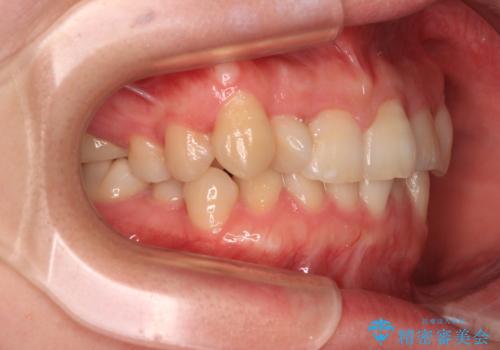

捻転の強い前歯 ワイヤー装置での非抜歯矯正

- 前歯のデコボコ、特に90度捻れている上顎前歯を気にして来院された患者様です。

捻転を解消する際に、歯列全体が前方に突出して出っ歯の仕上がりとなることが懸念されたため、補助装置を用いて上顎歯列全体を後方に移動する力をかけることとしました。

当初予定通り1年半ほどの治療期間で、非常に綺麗な歯列に仕上げることができました。